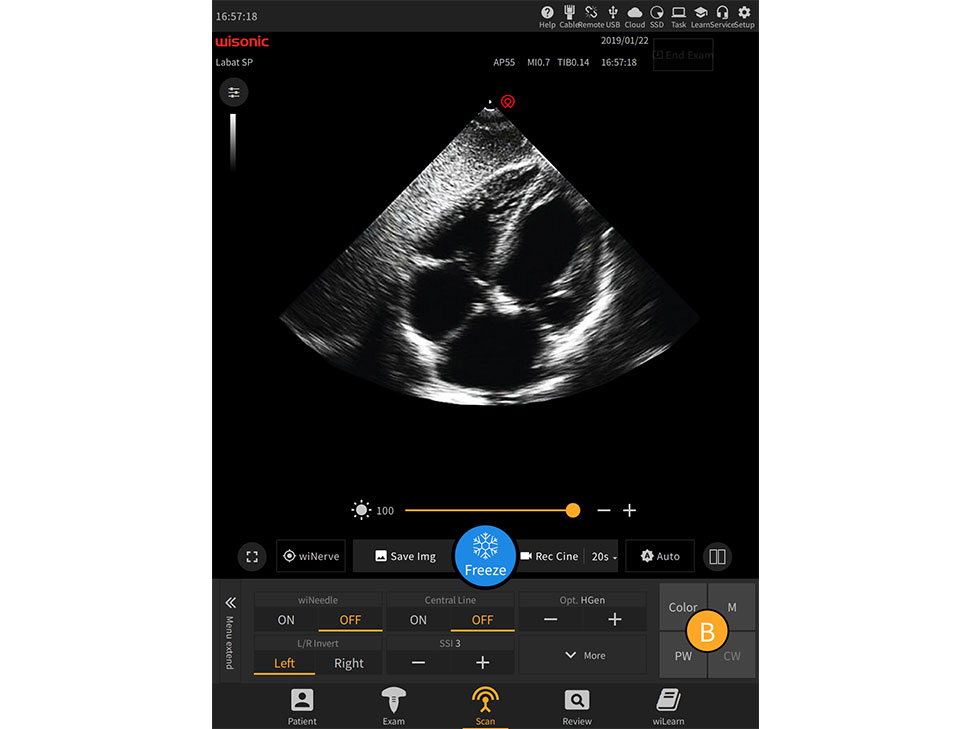

übersicht

wiNerve

Intelligente AI-Nervenerkennung

Erkennung in Echtzeit

Cloud-L?sung

Unterstützung mehrerer Nerven

Excellent Clinical Images

Anwendungsbilder